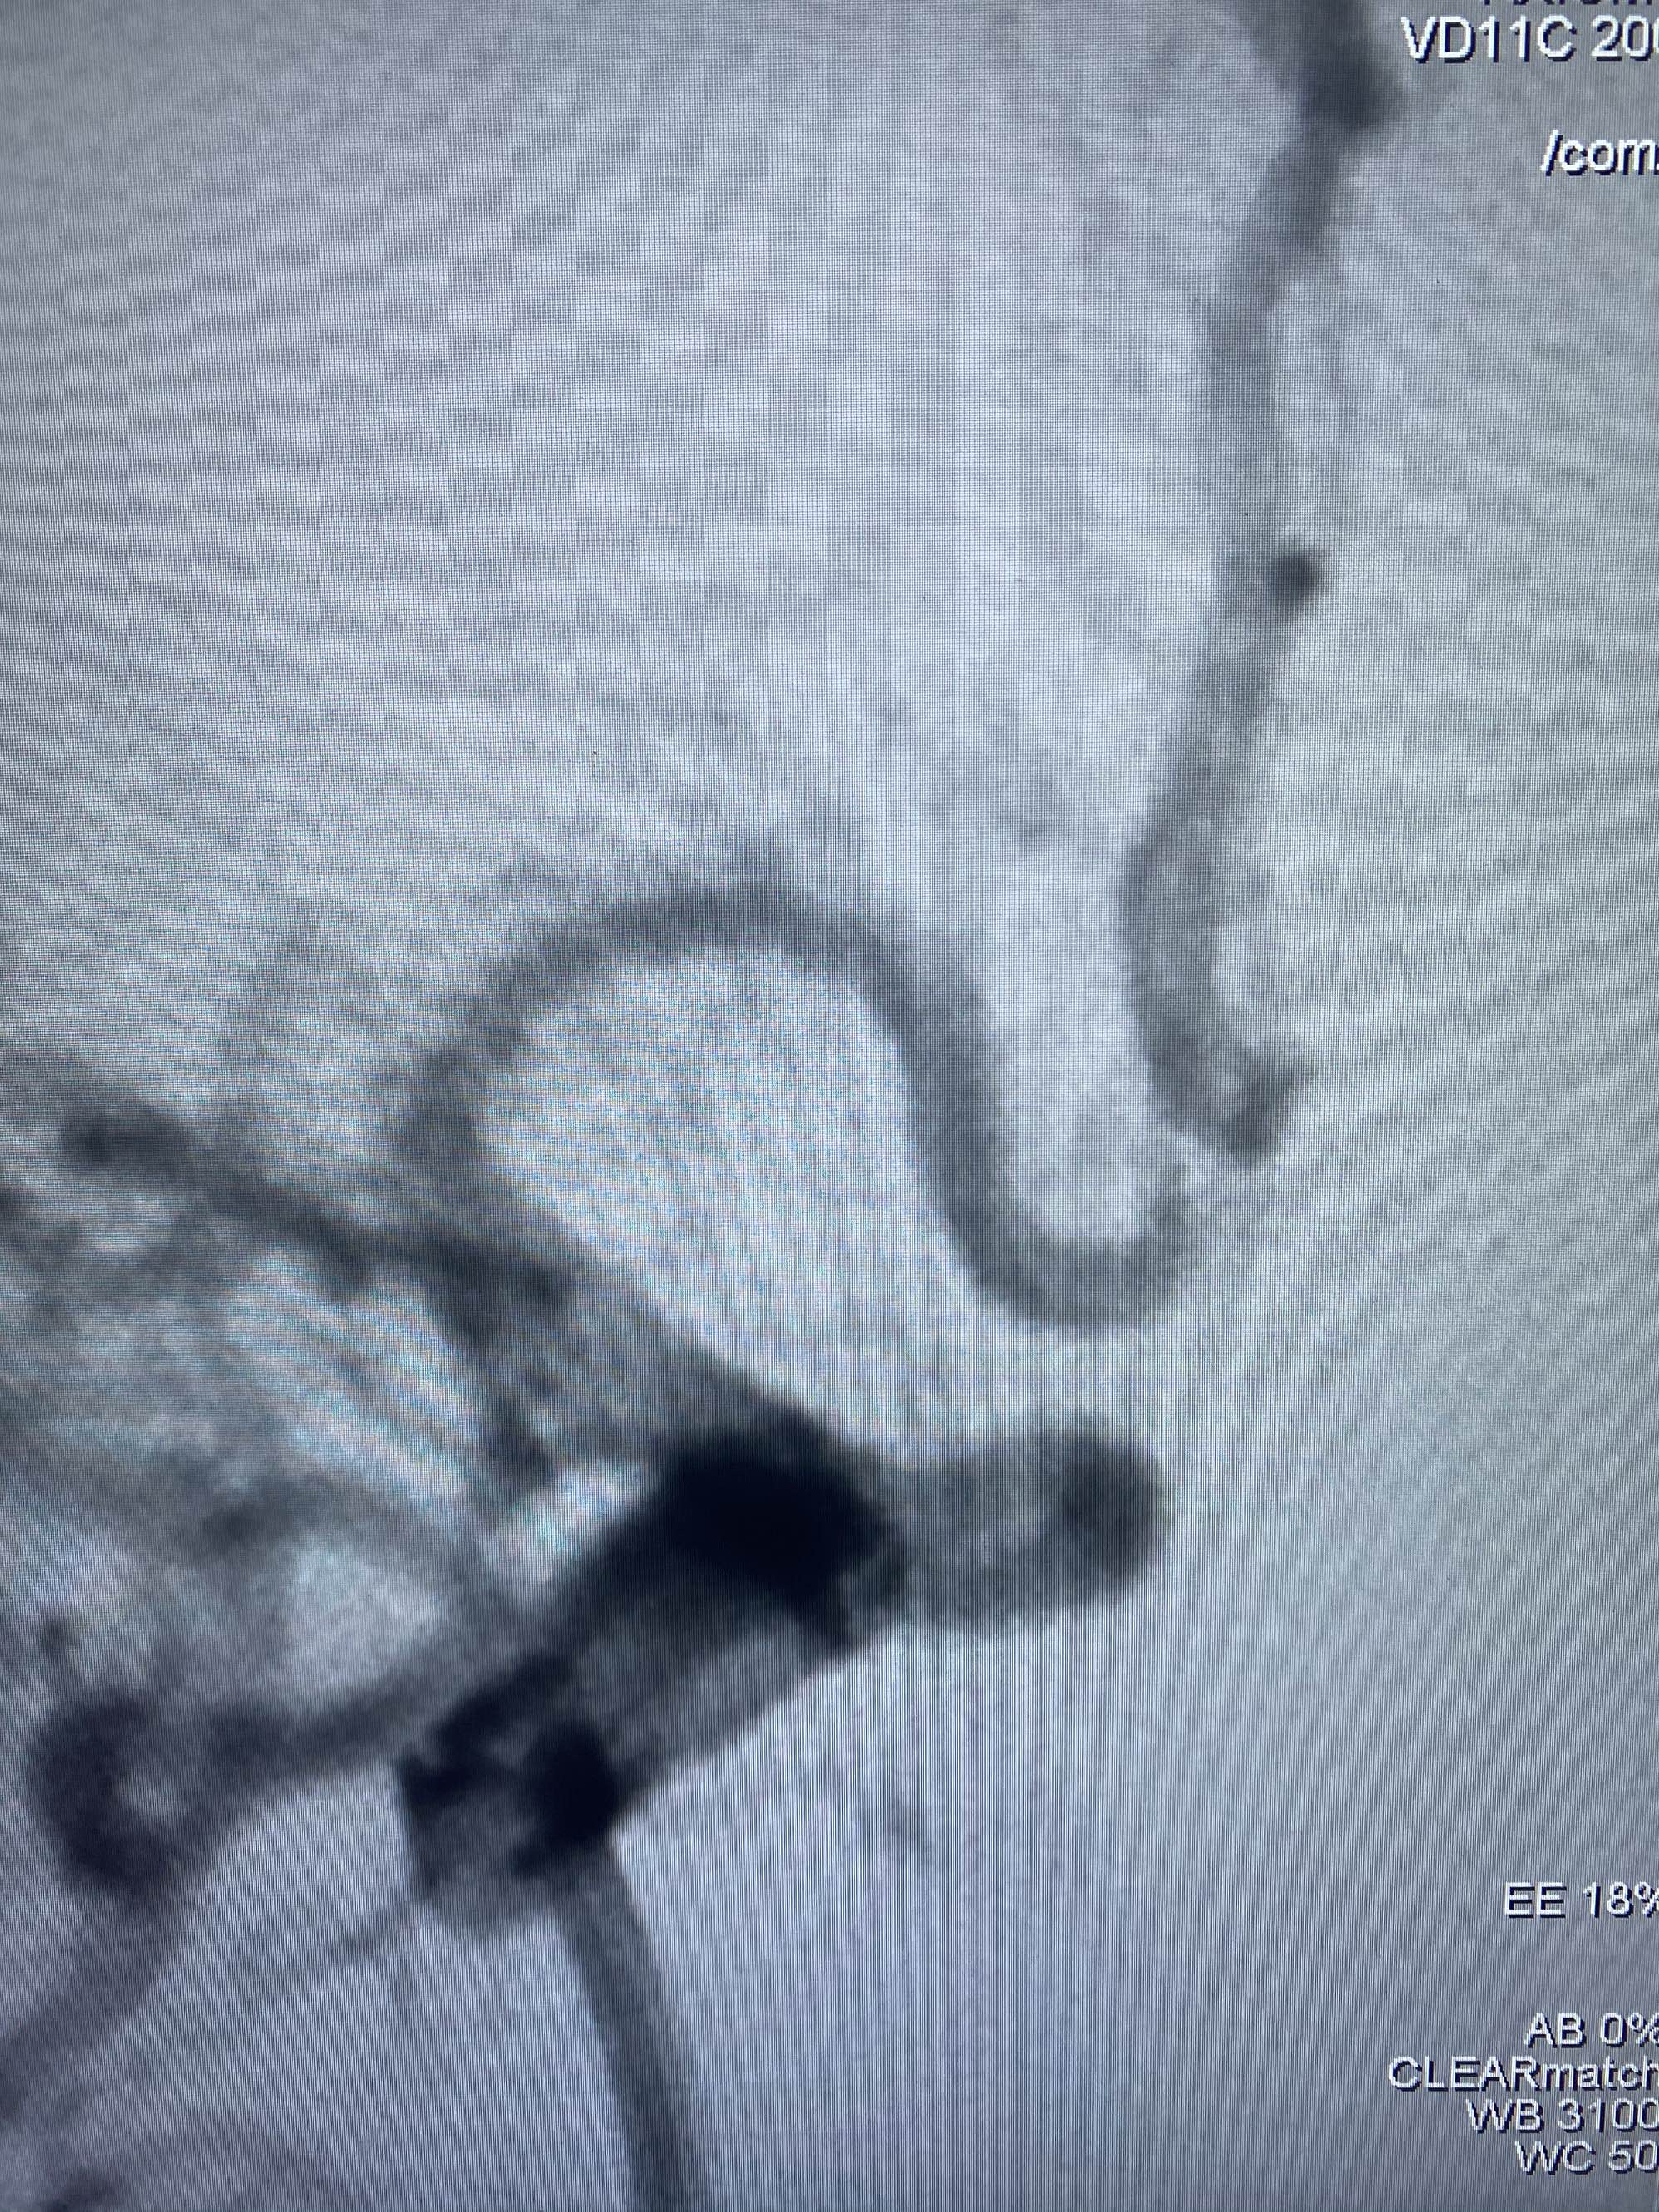

MLS,M79Y,sah,双侧MCA烟雾病,Heubner返动脉瘤,前交通段开窗,细支发出Heubner返动脉,瘤颈细长,瘤颈口比微导管细,弹簧圈2mmx3cm“隔山打牛”填塞治愈,Heubner返动脉保留。